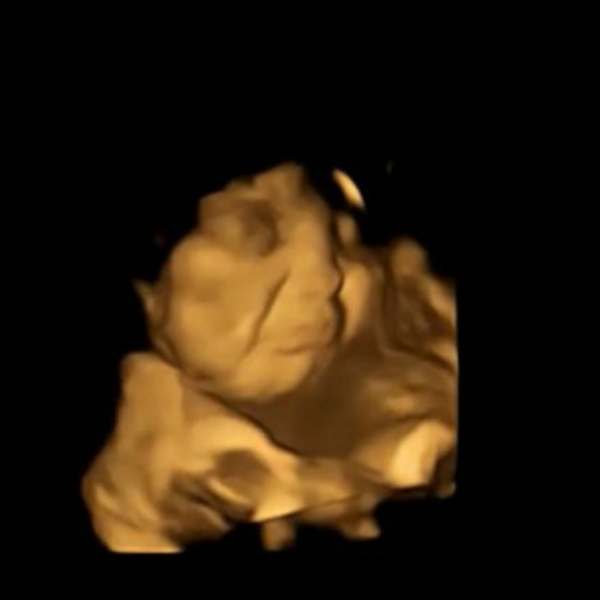

அதில் விரும்பிய உணவை தாய் உண்ணும் போது, சிசுக்கள் சிரித்த முகத்துடனும், பிடிக்காத உணவை உண்ணும் போது சிசுக்கள் தங்கள் முகத்தை அஷ்டக்கோணலாகவும் மாற்றுவதை மருத்துவர்கள் வீடியோ பதிவு செய்துள்ளனர்.

அதே சமயத்தில், கீரை, காய்கறிகள் கொடுக்கப்பட்ட பெண்களின் சிசுக்கள் தங்கள் முகத்தை அஷ்டக்கோணலாக வைத்திருந்தன. அதை பார்க்கும் போது சிசுக்கள் கோபமாகவும், வெறுப்பாகவும் இருப்பது நன்றாக தெரிகிறது. மேலும், பெரிய அளவில் அசைவும் இல்லாமல் கடமைக்கு உடலை நெளித்துக் கொண்டு இருந்தன. இந்த வெறுப்புணர்ச்சி பல மணிநேரங்களுக்கு இந்த சிசுக்களிடம் காணப்பட்டது. குறைந்தது 2 மணிநேரங்களுக்கு பிறகுதான் இந்தக் குழந்தைகள் அந்த வெறுப்புணர்வில் இருந்து வெளியே வருகின்றன.

மேலும், வயிற்றில் இருக்கும் சிசுக்கள் தங்கள் உணர்ச்சிகளை காட்டும் புகைப்படங்களையும், வீடியோக்களையும் மருத்துவர்கள் வெளியிட்டனர். இந்த புகைப்படங்கள் சமூக வலைதளங்கில் வைரலாகி வருகின்றன.